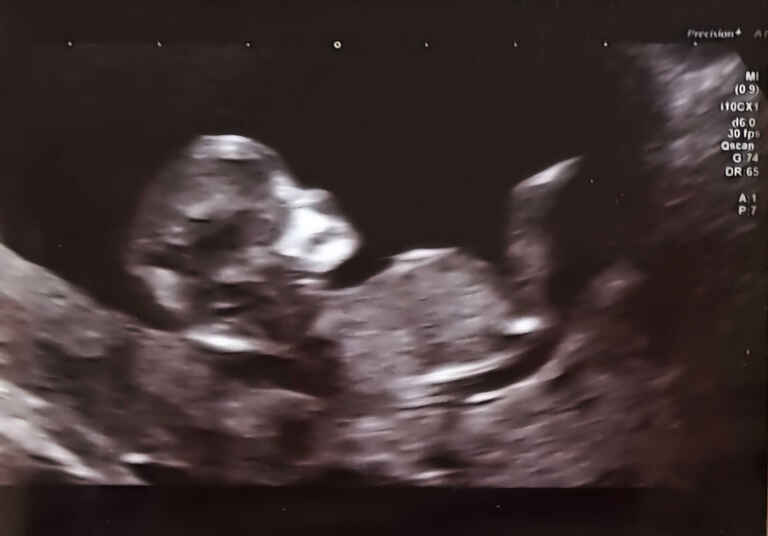

Photos 2024 January 21, 2024 · #photos#2024 « PreviousEmacs asynchronous copying using dired-async-mode Next »Opening Frequently Used Files More Efficiently using consult A new year, a new gallery! « PreviousEmacs asynchronous copying using dired-async-mode Next »Opening Frequently Used Files More Efficiently using consult